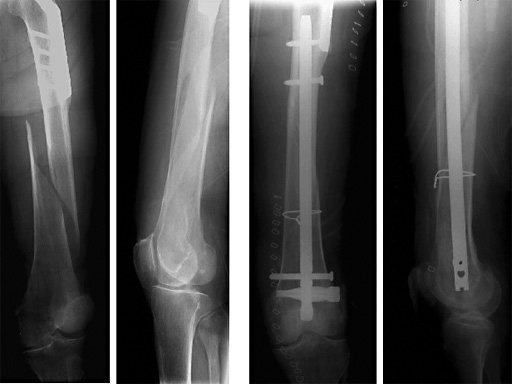

Female, 88 years

Distal Femoral Nail with Spiral Blade

Indications include extra-articular metaphyseal distal femoral fractures (32-A1 to C3) and supracondylar fractures and simple articular fractures (33-A1 to A3 and 33-C1 to C3.1).

The Spiral Blade enables significantly more stable distal interlocking than with conventional locking bolts due to the large load-bearing surface. It reduces cancellous bone compaction and lowers the risk of nail protrusion into the knee joint. The nail diameters are 9.0 and 10.0 mm for solid nails and 12.0 mm for cannulated nails.